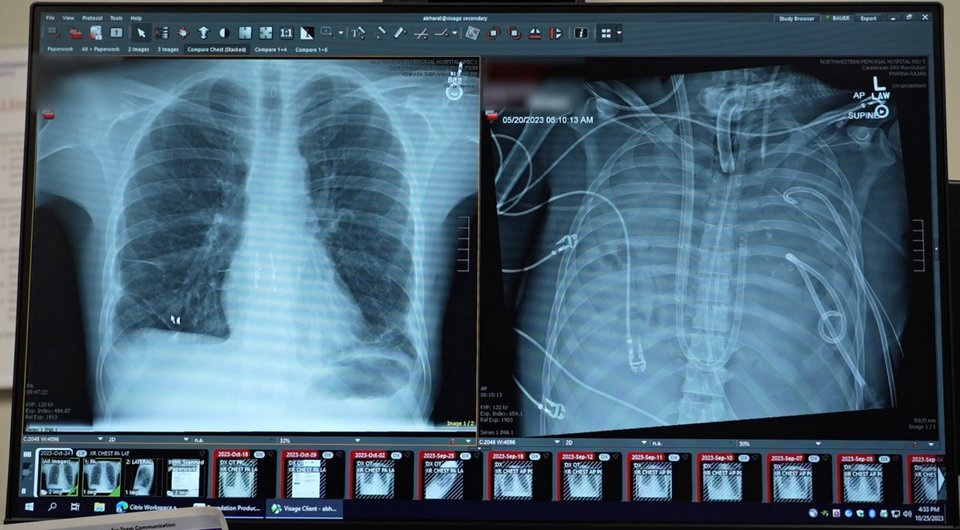

Американские исследователи сообщили о первом экспериментальном применении разработанного ими экстракорпорального полностью искусственного легкого. Аппарат позволил поддерживать жизнедеятельность и стабильное кровообращение 33-летнего пациента с удаленными легкими в течение 48 часов в ожидании трансплантации. Описание этого случая опубликовано в журнале Med.